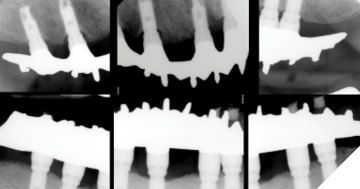

2. Tooth set-up try-in

- Hand-tighten abutment screws

- Radiographs to confirm seating

- Assess VDO, phonetics, esthetics, occlusion, cleansability, etc.

- Patient consent for processing

- Place healing abutments/MUA caps (or use previous provisional, if available)

3. Insertion

- Check for any acrylic flash, evaluate prostheses on articulator

- Insert prostheses and-tighten prosthetic screws

- Last opportunity to verify framework passivity

- Radiograph to confirm seating

- Torque following manufacturers recommendations

- Check occlusion, hygiene access, etc.

- Teflon + interim restoration in screw access channel (or composite resin)

4. Post-insertion check

- Check screw torque for any loss of preload (Kelly & Salinas 2017) and place final screw-access restorations as needed

Treatment sequence (Figs. 7-12):

- Initial records and periodontal therapy to manage peri-implant mucositis

- Final impression of Mx + Md to capture new RRR

- Occlusion rim appointment

- Tooth set-up try-in of Md complete denture and Md IS-FDP

- Insertion

- Post-insertion check